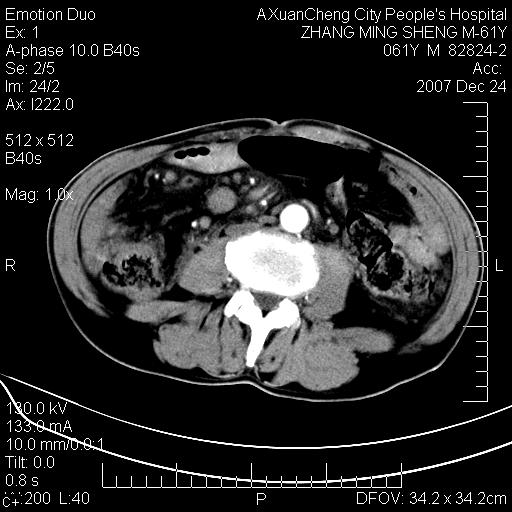

标题: CT11031:M61Y,胰腺占位 [打印本页]

标题: CT11031:M61Y,胰腺占位

大家侃侃门静脉和胆管系统怎么回事,肝内转移?

2,肝内多发结节状低密度占位,伴门脉及肠系膜上v栓子形成.考虑a;门脉及肠系膜上v血栓后肝改变.b;弥漫型肝癌伴门脉及肠系膜癌栓.

肝硬化,门脉高压,脾肿大;弥漫性肝癌,肝内、门脉、腹膜后淋巴结转移,肝内外胆管扩张,胰头区占位,建议mr检查

胰腺癌伴肝内转移;门脉、肠系膜上v癌栓形成。

考虑为:胰腺癌伴肝脏转移、腹膜后淋巴结转移,门静脉及肠系膜上静脉瘤栓形成。

胰体尾癌伴肝内转移,门静脉及肠系膜上静脉瘤栓形成.